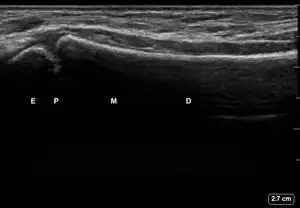

| 3 | ![]() |

![]() |